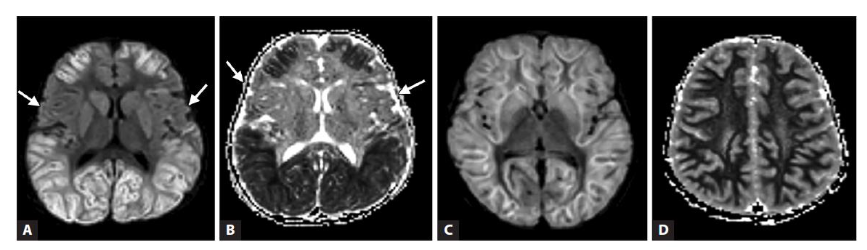

The diagnosis of ITES is based on the imaging findings in addition to the clinical features. MRI is preferred over CT brain. Diffusion weighted imaging and FLAIR sequences are key modalities in the imaging protocol.

In AESD, there is a biphasic pattern of illness which correlates with radiological evolution. The initial scans are usually normal followed by diffuse restriction of the frontal or fronto-parietal subcortical white matter with central sparing. Later scans show cerebral atrophy. Based on the imaging findings, Kamate et al suggested a change of the terminology to ALERD (Acute Leukoencephalopathy with restricted diffusion) as it depicts the condition better.

In ANEC/ANE1, there is involvement of bilateral thalami in the form of areas of diffusion restriction with haemorrhagic necrosis (‘trilaminar sign’). Involvement of midbrain, brainstem and cortex are also noted and have been associated with poorer outcomes. In milder forms of sporadic ANE, spontaneous resolution of lesions with residual hemosiderin deposits are noted with minimal sequelae.